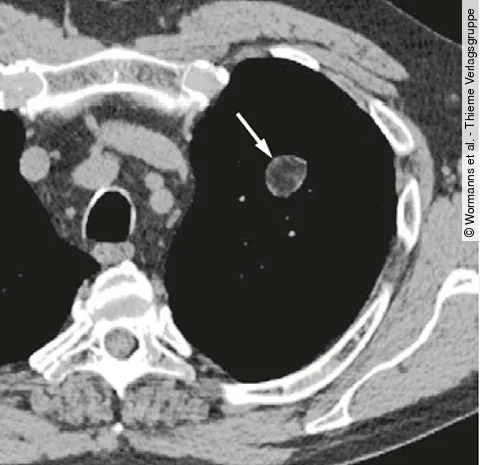

Ein 45-jähriger Patient stellt sich in Ihrer hausärztlichen Praxis vor, weil seit wenigen Wochen anfallsweise Gesichtsrötung, Herzrasen, Durchfälle und Bauchschmerzen wechselnder Intensität sowie Luftnot auftreten.